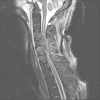

Despite promising advances in basic spinal cord repair research, no effective therapy resulting in major neurological or functional recovery after traumatic spinal cord injury (tSCI) is available to date. The neurological examination according to the International Standards for Neurological and Functional Classification of Spinal Cord Injury Patients (International Standards) has become the cornerstone in the assessment of the severity and level of the injury. Based on parameters from the International Standards, physicians are able to inform patients about the predicted long-term outcomes, including the ability to walk, with high accuracy. In those patients who cannot participate in a reliable physical neurological examination, magnetic resonance imaging and electrophysiological examinations may provide useful diagnostic and prognostic information. As clinical research on this topic continues, the prognostic value of the reviewed diagnostic assessments will become more accurate in the near future. These advances will provide useful information for physicians to counsel tSCI patients and their families during the catastrophic initial phase after the injury.